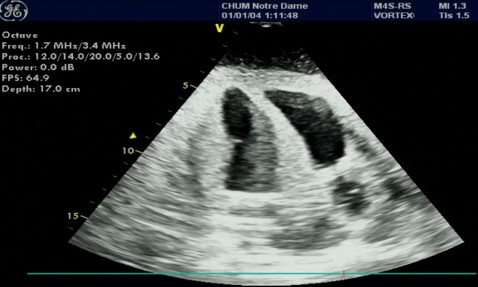

However, the development and deployment of DL models in such applications faces many challenges. To begin with, recognizing cardiac views in the TTE process is challenging due to subtle differences among various views [20]. Figure 1 illustrates three images of the apical four chamber view, a standard view of the heart. These images depict the same view but exhibit variances stemming from noise, speckles, and differences in US scanning machine and probe configurations.

Refer to caption

(a) Uncompleted Cardiac View

(b) Speckled Cardiac View

(c) Completed Cardiac View

Fig. 1: Different images of the apical four chamber cardiac view